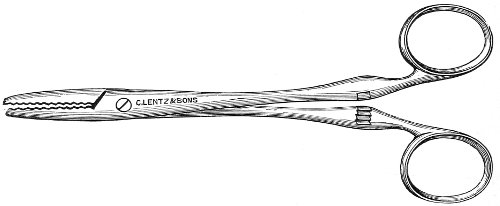

Fig. 24.—Emmet’s perineal scissors.

Fig. 25.—Curved scissors for denuding.

The secondary operation is performed at any time after cicatrization has occurred—often many years after the receipt of the injury. This operation is at present one of the commonest in gynecology, because the injury is not detected, is neglected, or is improperly repaired after labor. In the secondary operation an anesthetic is necessary. The mucous membrane must be removed or denuded on the posterior wall and about the mouth of the vagina, in order that the lacerated structures may be brought again in apposition. The denudation is best made by means of scissors curved on the flat (Figs. 24 and 25).

The strip of mucous membrane to be removed is picked up with a tenaculum (Fig. 26) or with tissue forceps 65 (Fig. 27); the scissors are placed with the blades parallel to the surface to be denuded, and the strip is cut away evenly, in one piece if possible. A similar contiguous strip is removed, and so on until the necessary surface is bare. Sponges in holders (Fig. 28) or continuous irrigation may be used to remove blood.